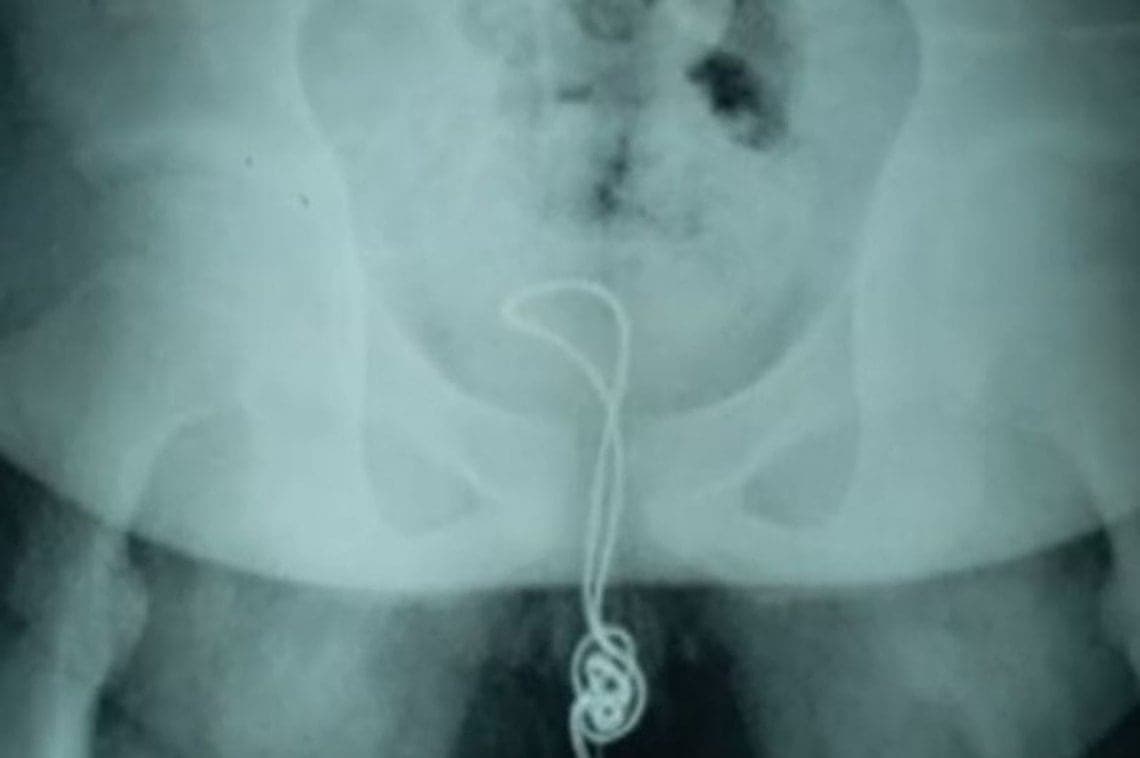

MundoAdolescente "curioso" se introdujo un cable USB que acabó enredado en su vejiga7 de julio de 2018